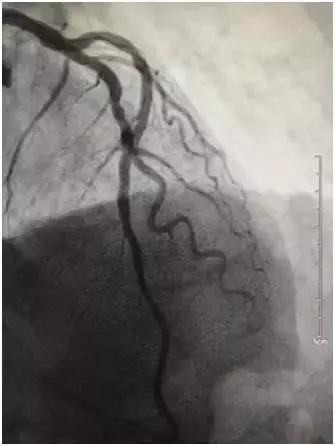

前降支中段置入支架一枚

病例1,李大爷今年64岁,平素身体健康,无高血压、糖尿病等病史,平素无吸烟史,由于生在农村,无论严寒酷暑,农活从未停息过,自觉身体很棒,随时笑口常开。近三四天自觉很疲乏,间感胸口隐隐疼痛,轻微活动即感胸痛明显加重,李大爷自认为“感冒”,卧床休息两天或服用点感冒药即可好转,可连续休息两天无好转迹象,入院前一晚(12月6日)夜间4点胸痛症状明显加重,持续不缓解,伴大汗淋漓,呼吸困难。立即送入当地医院,考虑“心梗”,于次日12时转至我院急诊科,我科会诊后诊断“急性心肌梗死”,考虑仍在急诊PCI治疗的时间窗内,立即启动导管室,通过绿色通道,急诊进行冠脉介入。造影显示左前降支近段99%狭窄,次全闭塞。随后予球囊扩张狭窄处,置入支架一枚,血流立即通畅,李大爷胸痛顿时明显缓解,生命体征平稳,转入监护室继续治疗。